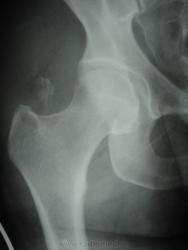

молодая женщина, спрыгнула со второго этажа при пожаре. Справа клиника ушиба, разможжение тканей, рваная рана бедра. травматологи написали отрывной перелом бедренной кости, в этом месте вижу впервые.

Отрывной перелом части большого вертела.

слева на вертеле тоже есть участок просветления. как эти кусочки поднялись так высоко, там же мышцы???

на счет большого вертела, похоже что да....